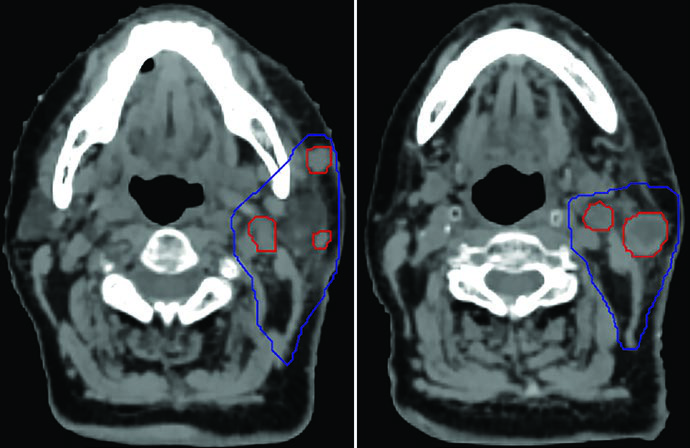

Recurrence in a centenarian. A 100-year-old woman with recurrent skin squamous cell carcinoma at the parotid and neck nodes. The GTV45 (red) encompassed gross disease, while the CTVn25 (blue) covered the nodal basin at high risk of relapse. She remained well for 6 months, then recurred regionally both inside and outside the low-dose field — demonstrating an inherent limitation of SBRT when extensive elective volumes are needed but not included. For comparisons with conventional head and neck approaches, see our article on larynx cancer delineation.